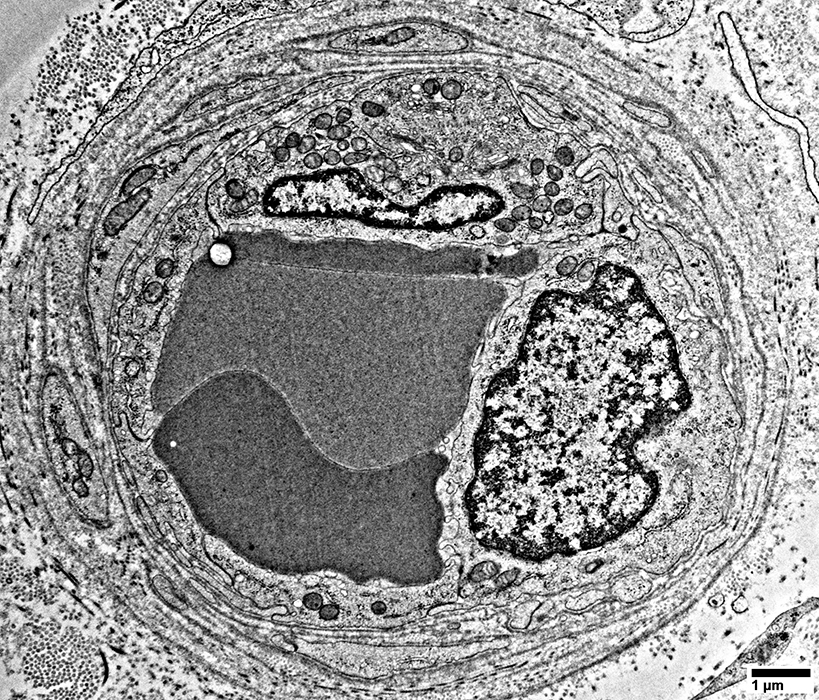

Endoneurial Cell: Degeneration

Neighboring Schwann cell process

Another small Schwann cell (Right) has collagen pockets

From: R Schmidt

Endoneurial Cells: Degeneration